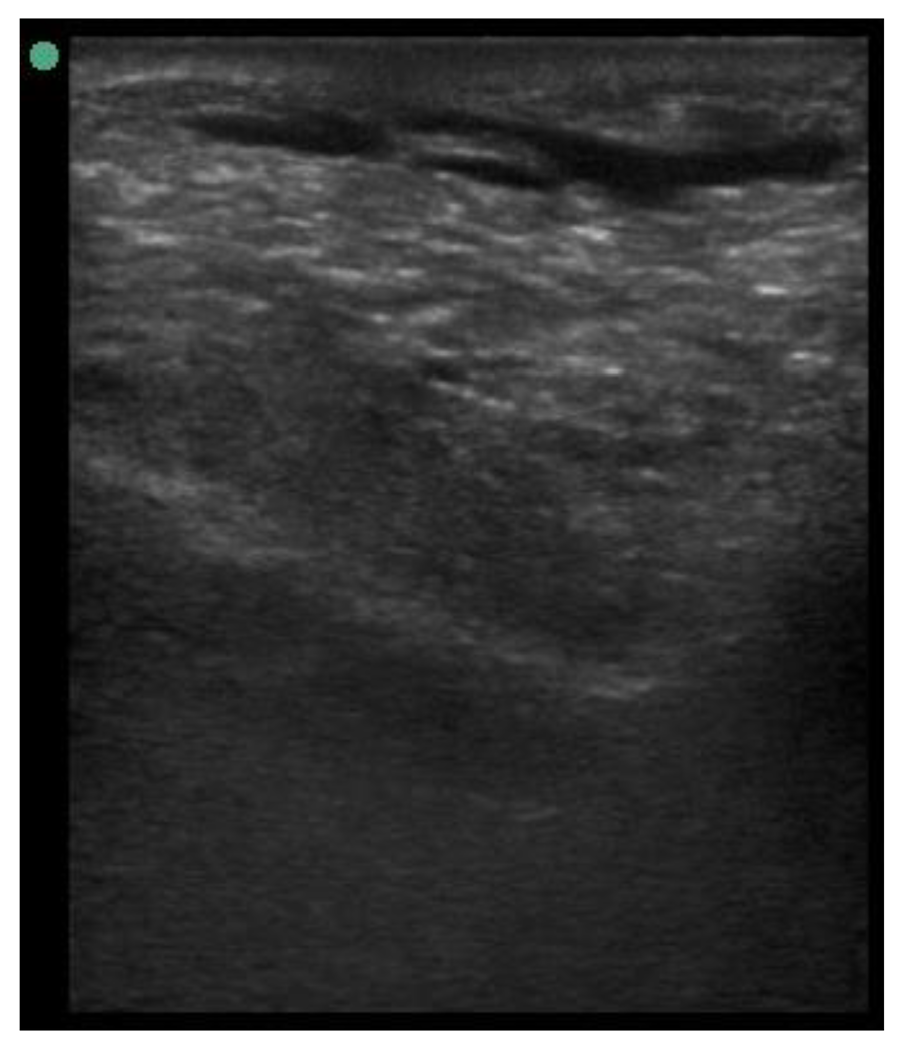

A minimum of three images were taken from each udder half. Images included the gland cistern, mammary parenchyma, putative fat pad and the boundary between the mammary gland and the abdominal wall. One image of suitable resolution per udder half, where all structures were identifiable and present was selected for image processing [27]. Udder halves with an udder palpation score of 4 or 5 (Table 1) at a specific time point (P107, L29 or L100) were considered “abnormal” [23] and were not included in the image selection (heavy: 1 ewe with 1 half and control: 2 ewes with 1 half each).

The image processing was undertaken using ImageJ software [28] as used by Abràmoff et al. [29]. The scales between pixels and millimetres were calculated based on the number of pixels, the scanning depth (mm), and the transducer width (mm) (Figure 4). This method relies on the ability of the operator to interpret and identify lines on the images. To standardize the assessment compartment depth, drawing templates were created for each time point as used by Molenaar et al. [30] and included four representative images from four different yearling ewes with and without the lines drawn for each compartment (Appendix A). The total depth of mammary gland conservative (MTc) was the smallest likely demarcation (abdominal wall) of the mammary gland (Figure 5a), and total depth of the mammary gland generous (MTg) was the largest likely demarcation of the mammary gland visible on the image [30] (Figure 5a). The MTc, MTg, fat pad (FP), parenchyma (PAR), and gland cistern (GC) depths were estimated at the deepest point for each sub-compartment, excluding the skin layers, using the straight tracer (Figure 5a) and were expressed in millimetres.

Figure 5.

(a) Demonstration of delimitations of the mammary total depth conservative (MTc) and generous (MTg), mammary gland cistern (GC), parenchyma (PAR) and the fat pad (FP) and (b) Demonstration of randomly positioning of regions of interest (1, 2, 3) in the parenchyma.

Appendix A. Drawing Templates of Mammary Ultrasound Images in Late Pregnancy, Early Lactation and Weaning in Yearling Ewes

Drawing template of mammary ultrasound images in late pregnancy (107 days of pregnancy; P107) in four different yearling ewes.